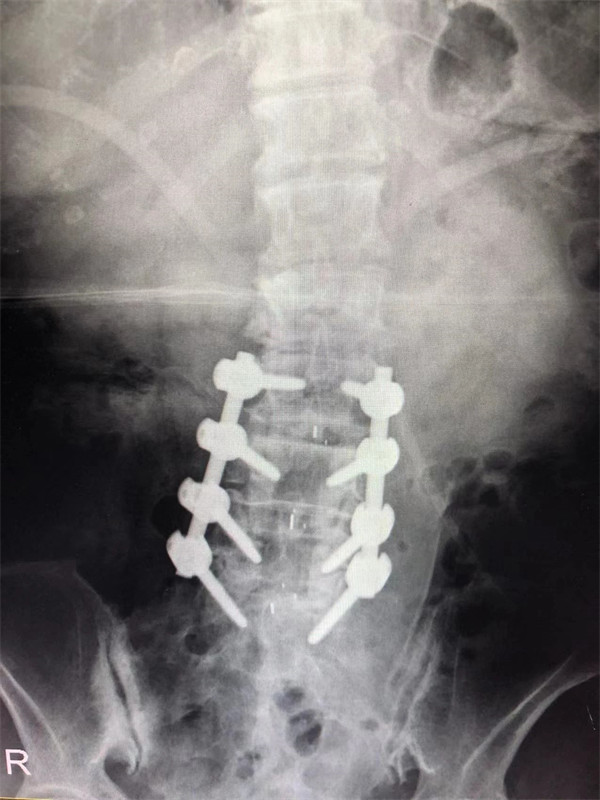

手術(shù)后↓

戈才華主任團隊討論病情及手術(shù)風險,并與麻醉科醫(yī)生多次討論術(shù)中麻醉風險,經(jīng)過詳盡周密的布置之后,最終給阿婆在全麻下進行腰3/4,4/5,腰5/骶1腰椎椎體間融合術(shù)。